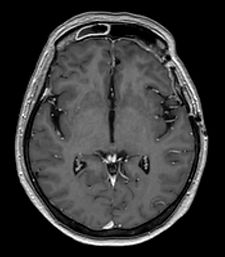

Meningioma

Meningioma pieres pamatnē pirms operācijas

Pēc operācijas meningiomas vairs nav